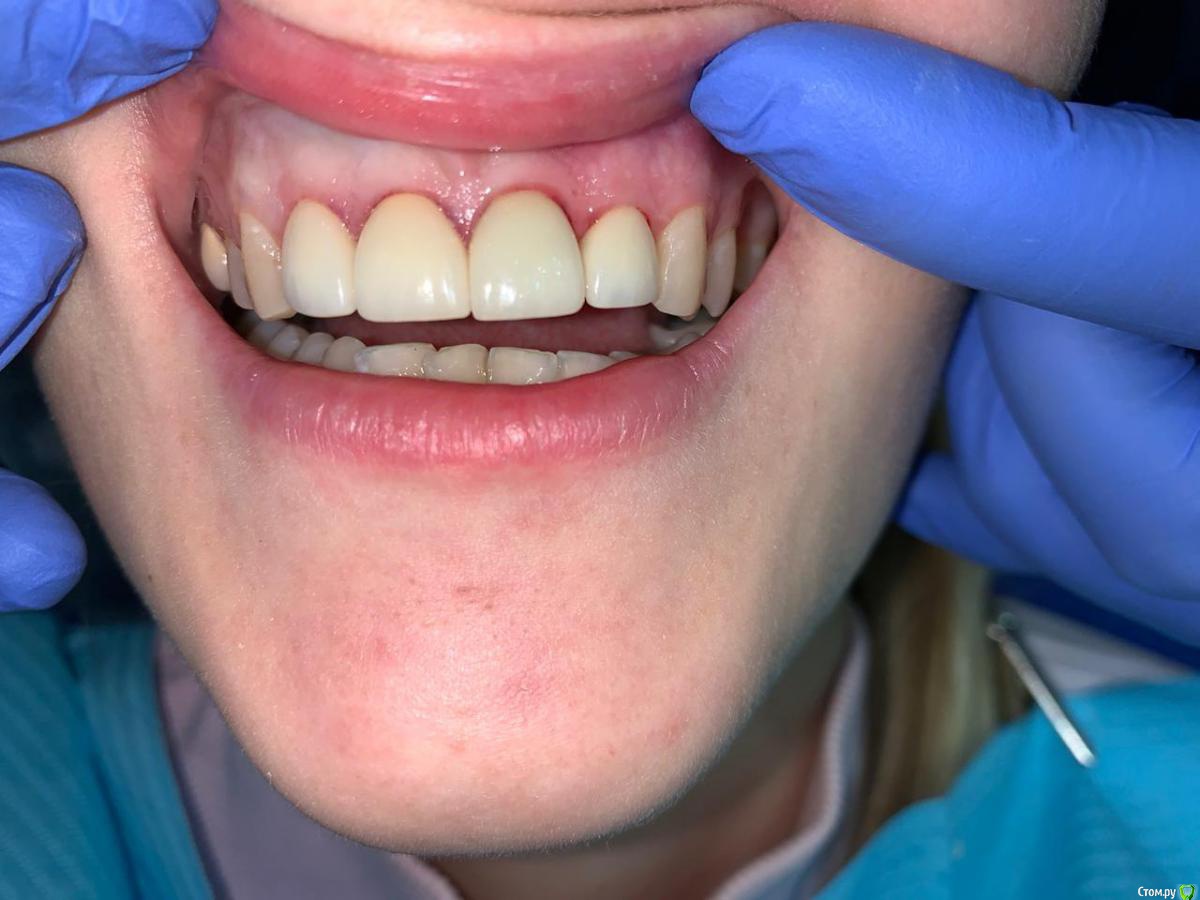

В декабре 2019 г мне поставили коронки emax. И на соседние 2 зуба- виниры (чтоб смотрелось норм)

Результат постановки коронок меня не устроил. Зубы поставлены как будто под наклоном и между коронками в одном месте появился огромный десновой сосочек, который мешает жить, при разговоре и слюна вылетает и свистеть можно) врач уверяла, что зарастёт за 2 недели. Но прошло 3 месяца, ситуация не изменилась.

Я обратилась к другим ортопедам за советом, может мне поставили коронки не так как надо? Почему щель? И большинство ответов было таким- коронка одна поставлена не плотно. И вообще чтобы поставить качественно коронки , нужна ортодонтия.

У вас есть скривление зубных дуг в разных плоскостях, для правильного функционирования, необходимо провести анализ окклюзионных взаимоотношений чтобы принять решение на сколько вам необходима ортодонтическая подготовка, и сделать прицельные снимки в области установленных керамических конструкций, что бы понять в чем причина ваших беспокойств, на фото я не вижу огромного десневого сосочка.